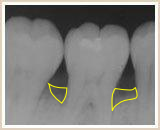

歯ぐきから血が出ていないから大丈夫と思われているかもしれませんが、歯周病は血が出ていなくても進行しています。歯周病はサイレントキラーと呼ばれるほど自覚症状がなく進行してく病気です。

その背景にも関連し、知らず知らずのうちに歯周病が進行し、日本の成人では約80%が歯周病にかかっていると言われています。

歯周病のこと~日本人の80%は歯周病です~